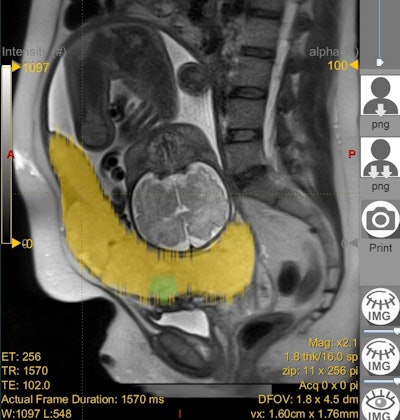

ADC values were obtained from the area above the bladder and the entire placenta on a midline sagittal image by two readers. Heterogeneity of the placenta and placental dark bands were also noted. A pathological diagnosis was obtained from the medical records. Texture study of a sample size of 33 images was also analyzed using a radiomics program (LIFEx) by a single reader.